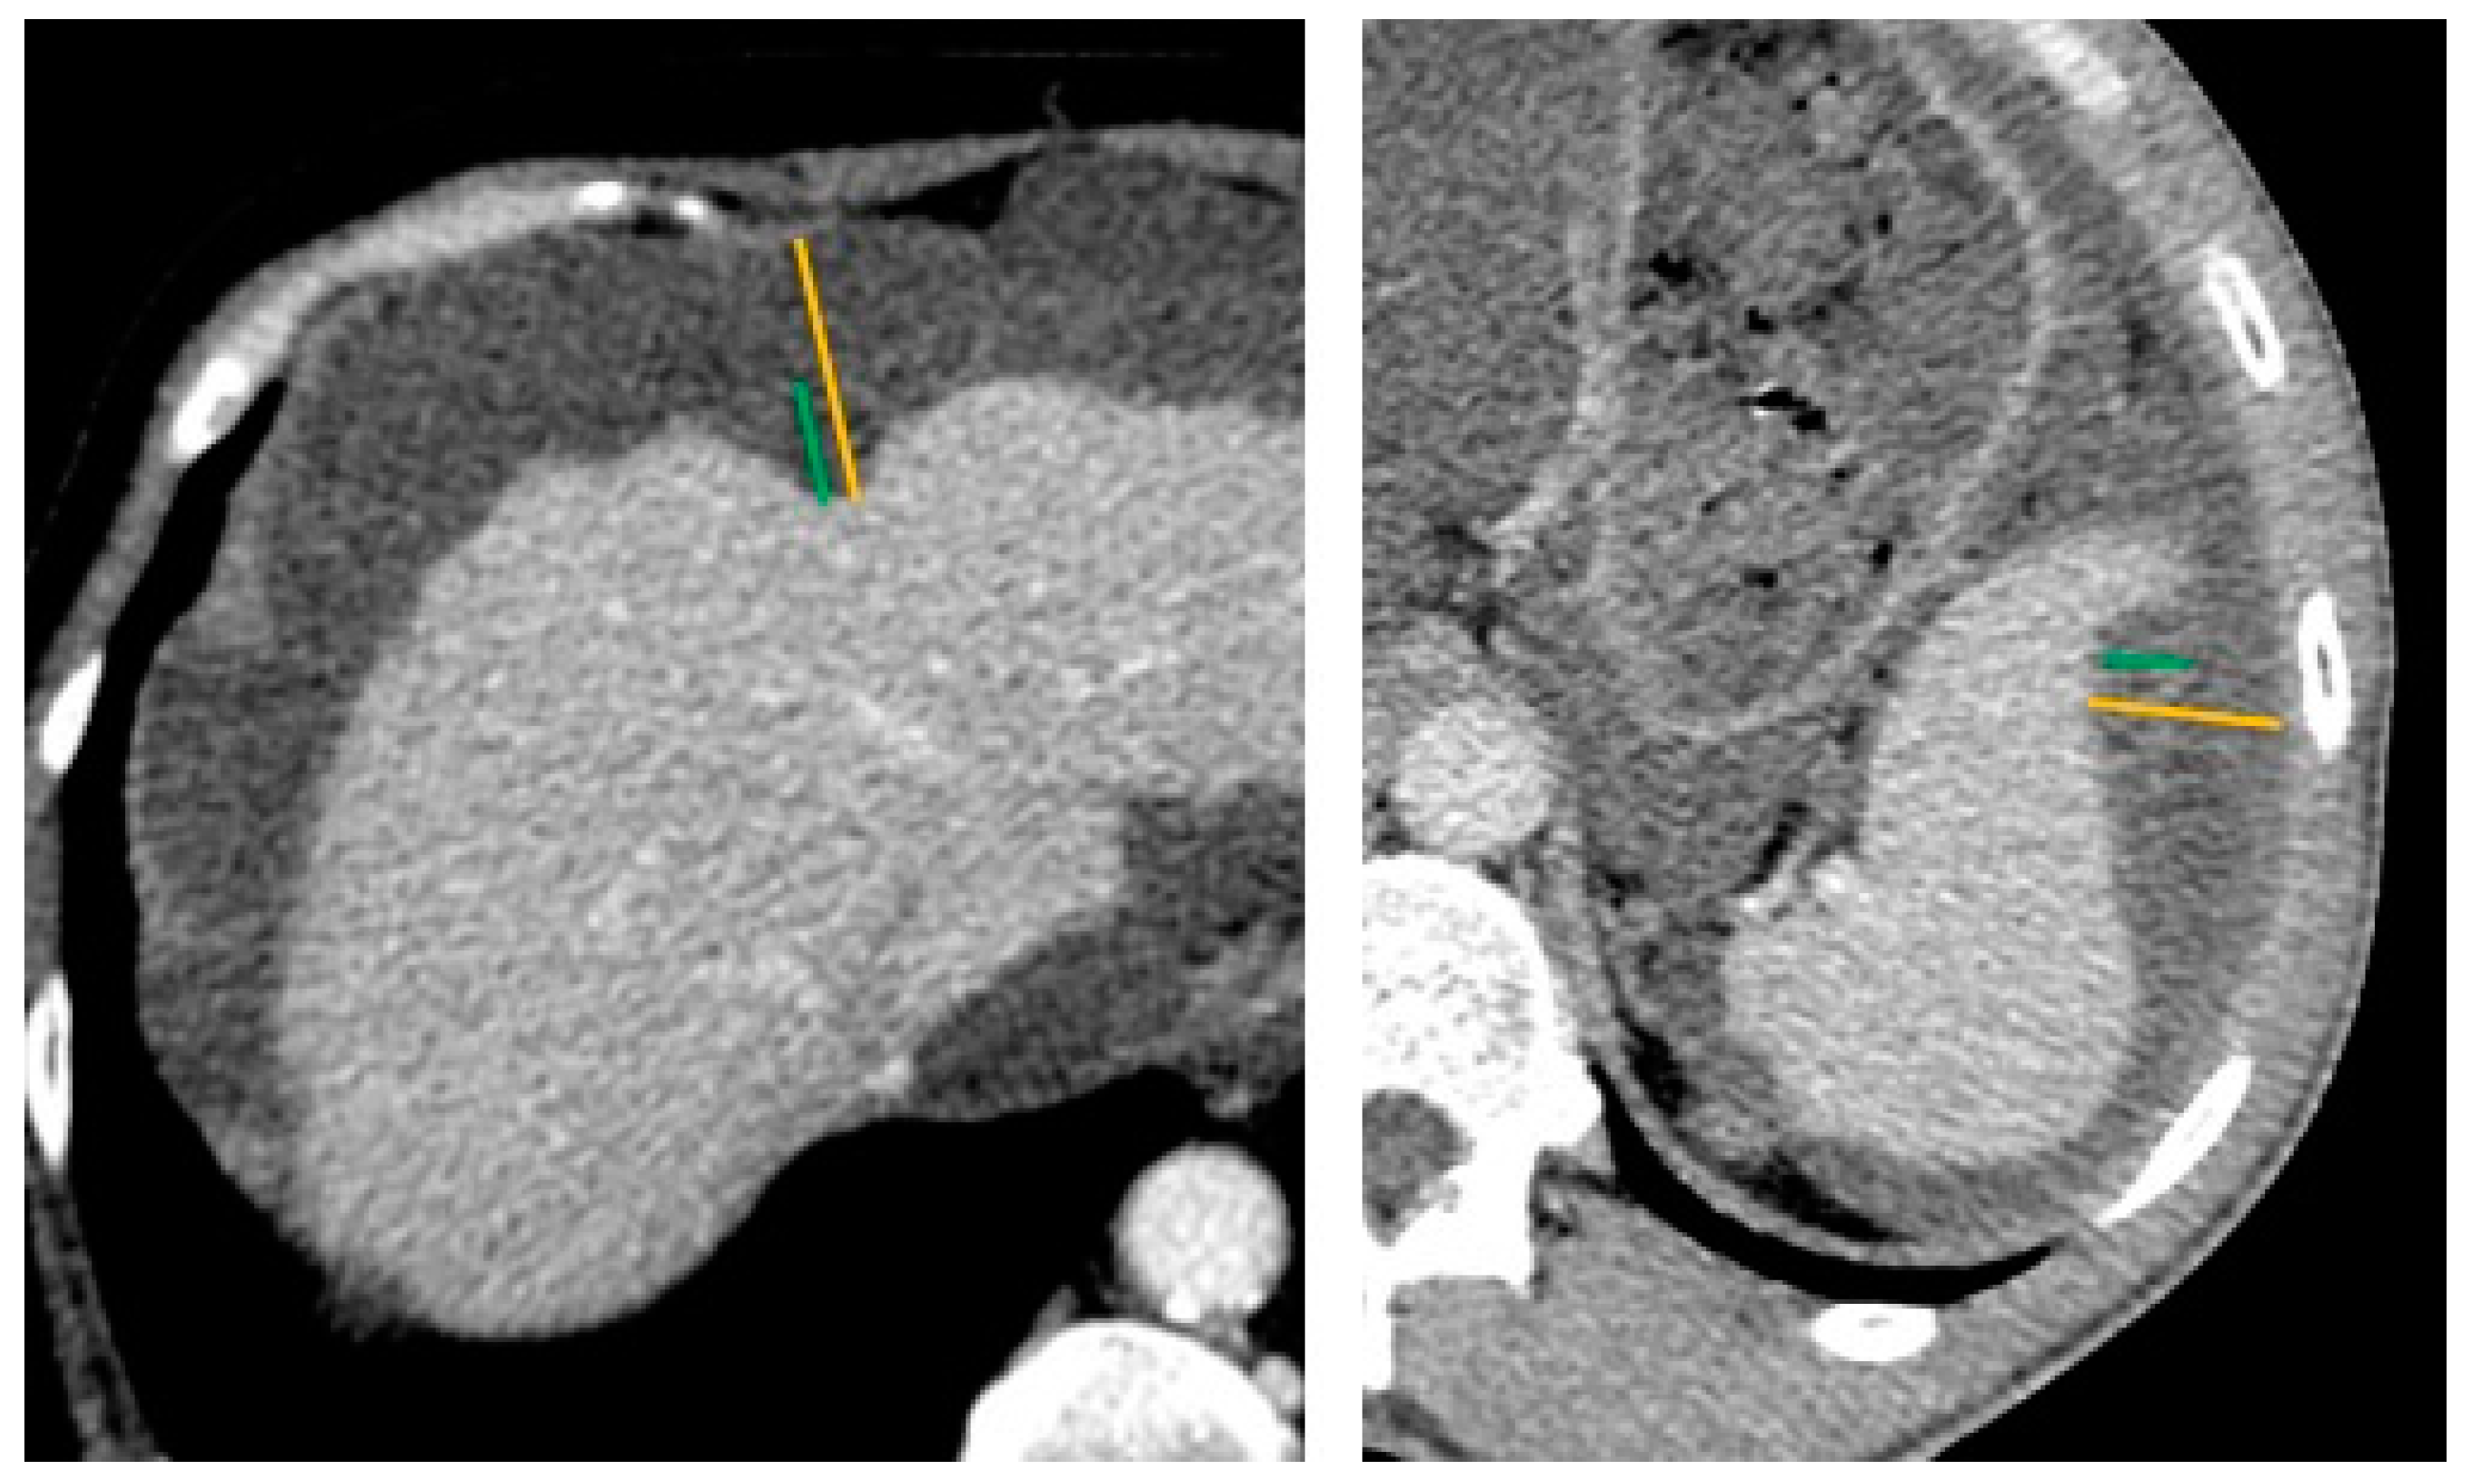

2.2. Preoperative CT-Scan Protocol and Image Analysis

| Liver scalloping 1 | ||||||||

| max depth (mm) | 11.0 [7.0, 17.0] | 21.0 [11.5, 24.0] | 71 (55%) | 0.007 | 11.0 [7.0, 17.0] | 13.5 [10.0, 24.5] | 52 (53%) | 0.2 |

| max depth Hotta (mm) | 14.0 [8.5, 27.0] | 23.0 [18.0, 32.5] | 71 (55%) | 0.038 | 14.0 [7.0, 26.0] | 15.5 [10.8, 25.0] | 52 (53%) | 0.4 |

| max length (mm) | 50.0 [32.5, 66.0] | 60.0 [40.0, 80.0] | 71 (55%) | 0.3 | 48.0 [35.0, 70.0] | 60.0 [43.2, 66.5] | 52 (53%) | 0.3 |

| ratio max depth/length | 0.2 [0.2, 0.4] | 0.4 [0.2, 0.5] | 71 (55%) | 0.10 | 0.2 [0.2, 0.4] | 0.3 [0.2, 0.4] | 52 (53%) | >0.9 |

| Splenic scalloping 1 | ||||||||

| max depth (mm) | 10.0 [8.0, 12.0] | 12.0 [10.0, 15.0] | 89 (69%) | 0.3 | 12.0 [10.0, 13.5] | 9.0 [7.0, 10.0] | 67 (68%) | 0.014 |

| max depth Hotta (mm) | 11.0 [9.0, 22.0] | 17.0 [11.0, 25.0] | 89 (69%) | 0.3 | 14.0 [10.0, 23.5] | 12.0 [7.0, 18.0] | 67 (68%) | 0.3 |

| max length (mm) | 40.0 [30.0, 47.0] | 30.0 [20.5, 41.5] | 89 (69%) | 0.2 | 40.0 [30.0, 60.0] | 28.0 [17.0, 35.0] | 67 (68%) | 0.019 |

| ratio max depth/length | 0.3 [0.2, 0.3] | 0.4 [0.3, 0.7] | 89 (69%) | 0.013 | 0.3 [0.2, 0.4] | 0.3 [0.3, 0.6] | 67 (68%) | 0.4 |